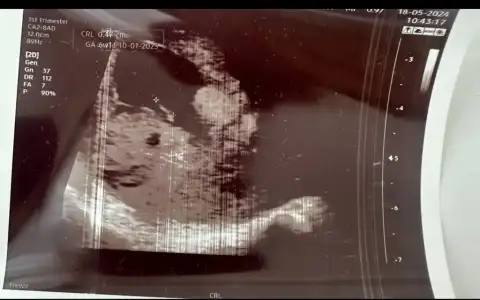

Erkek gibi geldi bana :)Selamm 10+4 haftalık bir ultrason görüntüm var bilenlerden cinsiyet tahmini alabilir miyiiimm

Selamm 10+4 haftalık bir ultrason görüntüm var bilenlerden cinsiyet tahmini alabilir miyiiimm

Kız